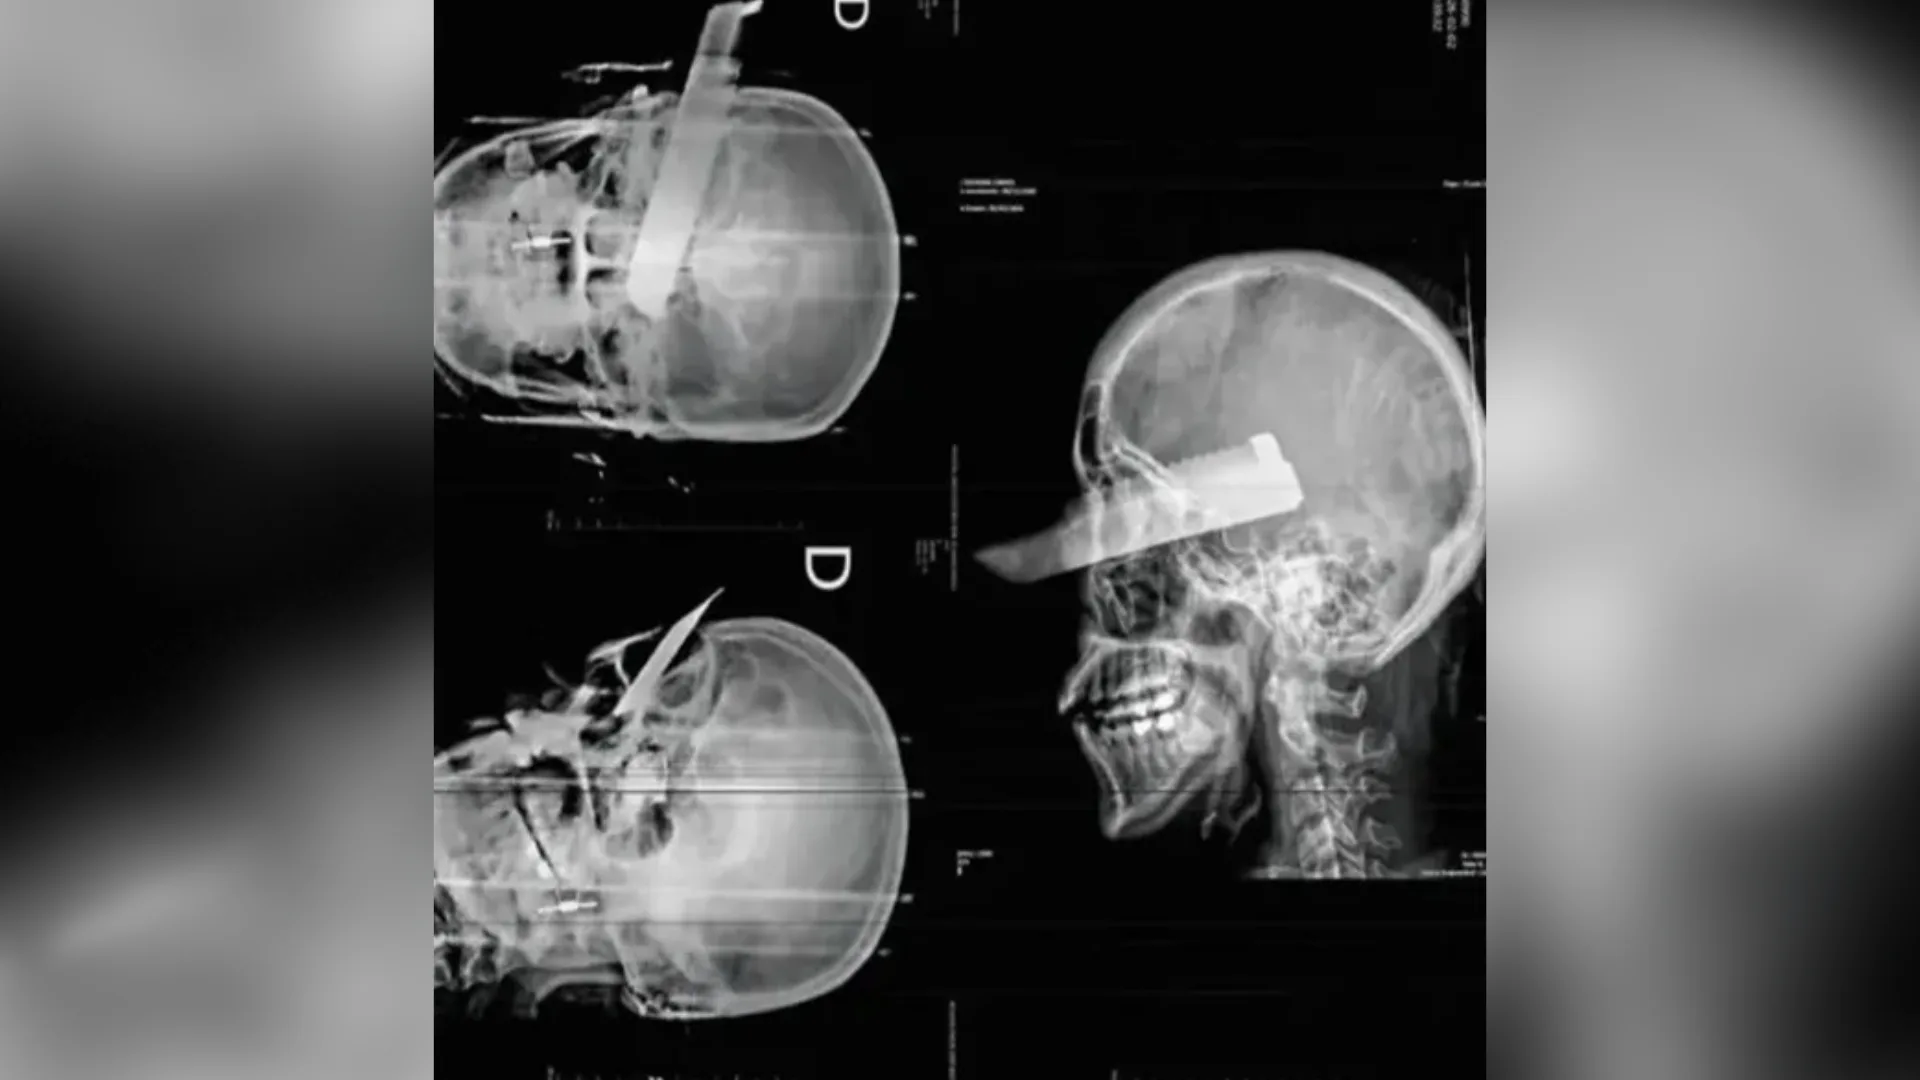

A Justiça decretrou a prisão preventiva do homem suspeitoinvestigado por atacar a companheira com uma facada no rosto em São Carlos, no Oeste de Santa Catarina. A decisão foi tomada na terça-feira (3), durante uma audiência de custódia, atendendo o pedido do Ministério Público de Santa Catarina (MPSC).

De acordo com as autoridades policiais, o crime ocorreu na tarde de segunda-feira (2), na residência do casal. Durante uma tentativa de fuga da vítima, o suspeito teria desferido um golpe de faca, atingindo o olho direito da mulher.